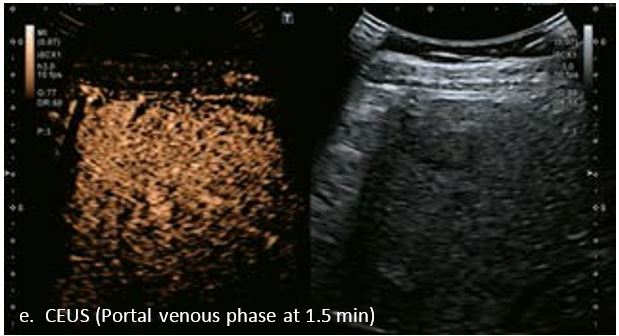

LI-RADS 4 множинні ГЦК

Це випадок 60-річної жінки з декомпенсованим цирозом печінки з асцитом. На сірошкальному зображенні можна виявити два вогнищевих ураження, розміром 21 мм і 10 мм відповідно, розташовані в сегменті 5. Оскільки дослідження методом зсувної хвилі на апараті Canon виконується штовхаючим імпульсом, пацієнтам з асцитом не можна проводити дослідження за допомогою зсувної хвилі, для визначення стадії фіброзу. На ранній артеріальній стадії гомогенне гіперехогенне підсилення спостерігається в обох ураженнях. Ураження є ізоехогенними в портальній венозній та пізній фазах, вимивання не спостерігається через 6 хвилин після ін'єкції, тому ці ураження були класифіковані як LI-RADS 4, ймовірна ГЦК. Важливо знати, що LI-RADS 5 - це ГЦК зі 100% вірогідністю, і вона не потребує біопсії. Значна кількість LI-RADS M (ймовірно або точно злоякісні, але не специфічні для ГЦК) і LI-RADS 4 (ймовірна ГЦК) насправді являються ГЦК.

Малюнок 11